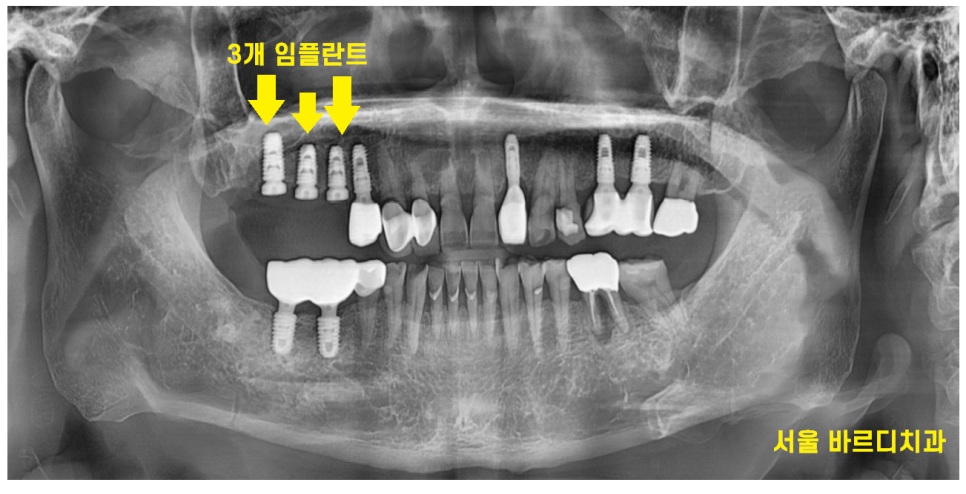

예전에 치아가 빠지고 씌울 때는

2개 치아 -> 3개 머리 브릿지 형태로 하셨지만

20년만에 치료하시는만큼

더 튼튼하게 씹을 수 있도록

치아 개수대로 계획을 잡아드렸습니다.

3개 치아 빠진 개수만큼

고덕동 임플란트

진행해드렸습니다.

이제 씹는 맛을 훨씬 더

잘 느끼실 수 있을겁니다.